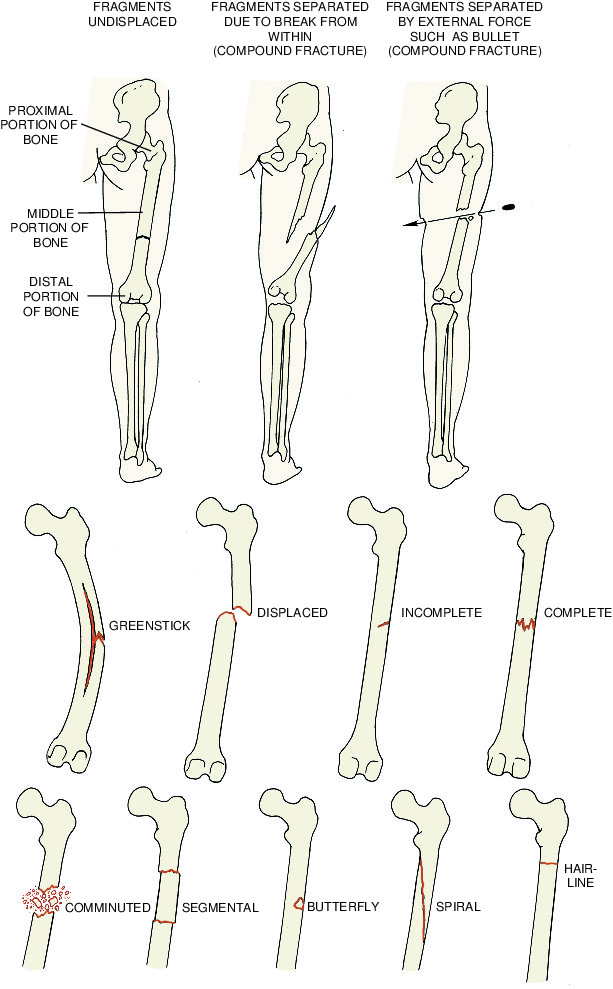

There are different types of foot fractures, learn how to identify each Pedal Fracture Definition The coffin bone, also known as the pedal bone or distal phalanx, is a small bone within the horse’s hoof. Pedal bone fractures often occur as a result of a sudden traumatic injury to a horse’s foot. Fractures of the distal phalanx (pedal bone) usually occur as a result of trauma such as kicking a solid object, standing on a. Pedal Fracture Definition.

What Are The Different Types Of Bone Fractures Pedal Fracture Definition Pedal bone fracture the coffin bone, also known as the pedal bone, third phalanx, distal phalanx, and os pedis , is located in the horse's foot. Fractures of the distal phalanx (pedal bone) usually occur as a result of trauma such as kicking a solid object, standing on a stone or fast exercise on hard ground. Pedal bone fractures often. Pedal Fracture Definition.

Types Of Fractures Images Pedal Fracture Definition It is the anatomic equivalent of the bone that. Fractures of the distal phalanx (pedal bone) usually occur as a result of trauma such as kicking a solid object, standing on a stone or fast exercise on hard ground. The coffin bone, also known as the pedal bone or distal phalanx, is a small bone within the horse’s hoof. Looking. Pedal Fracture Definition.

Complete Fracture Diagram Pedal Fracture Definition Diagnosis is made with plain radiographs of the ankle. Fractures of the distal phalanx (pedal bone) usually occur as a result of trauma such as kicking a solid object, standing on a stone or fast exercise on hard ground. The coffin bone, also known as the pedal bone or distal phalanx, is a small bone within the horse’s hoof. Ankle. Pedal Fracture Definition.